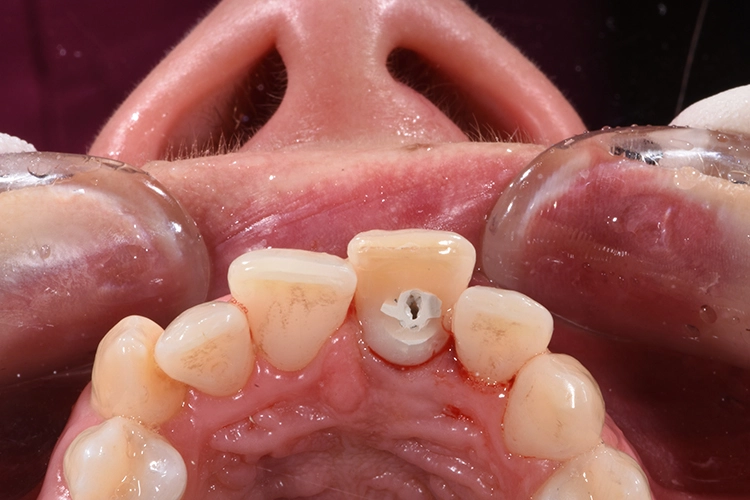

Fall 3: Sofortimplantation

Zu unserem Ausgangsbefund zählt die sechs Punkt-Taschenmessung, die Vitalität und Perkussionsprobe sowie ein Röntgenbild. Besonders wichtig ist in diesem Zusammenhang auch die genaue Anamnese des Patienten.

Dr. Blume

Deutlich auffallend und für die Patientin sehr wichtig war die anatomisch individuelle Zahnstellung des Zahnes 11. Um dem Wunsch der Patientin auf eine für ihr Umfeld unauffällige Behandlung gerecht zu werden, entschieden wir uns gemeinsam für eine Sofortimplantation mit einer provisorischen Sofortversorgung des Implantates. Kein Provisorium kommt der Natur so nah wie die Natur selbst und daher planten wir die Umarbeitung der Zahnkrone 11.

Nach der Lokalanästhesie wurde zunächst ein Kunststoff Jig hergestellt, der die Inzisalkante des Zahnes 11 mit denen der Nachbarzähne verbindet. Dieser dient zur späteren Positionierung der Zahnkrone, wenn diese zum Provisorium umgearbeitet wird und mit dem Implantat verbunden wird. Dieser Schritt ist besonders wichtig, da es für ein unauffälliges postoperatives Ergebnis auf die korrekte Positionierung des Zahnes ankommt und die Positionierungshelfer das Handling und den adhäsiven Verbund unglaublich vereinfacht (Abb. 20 und 21).

Anschließend wurde der durch die externe Resorption stark angegriffene Wurzelrest schonend entfernt. Bei der Sofortimplantation kommt es auf den Erhalt der lokalen knöchernen Bedeckung an.

Die Alveole wird von Granulationsgewebe gesäubert und direkt postoperativ durch ein Kleinröntgen auf Wurzelreste kontrolliert. Die Aufbereitung des Implantatbettes und die Implantatinsertion erfolgt im apikalen Bereich tendenziell eher palatinal. Im Bereich der Implantatschulter wurde ein Abstand von 2,5 mm zur vestibulären Lamelle eingehalten.